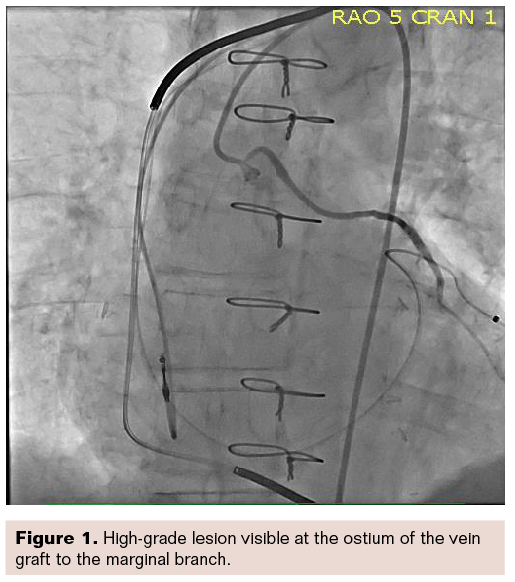

The patient had two high-grade lesions. One was in the ostium of the vein graft to the marginal branch (Figure 1), visible at the tip of the catheter, where the vein comes off the aorta.

We were able to intervene on that vein graft using relatively shallow angles and of course would expect the views to be clear, because the imaging does not require penetrating a lot of tissue. Figure 1 is the diagnostic injection. Figure 2 is the same right anterior oblique (RAO) view, but steeper and more angulated at a 38-degree angle. Note the image is still quite clear in this fairly obese person, with image quality almost identical between the two views shown in Figures 1-2.